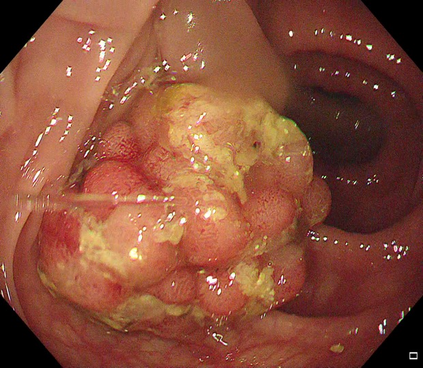

Polyps are early cancer indicators, so assessing occurrences of polyps and their removal is critical. They are observed through a colonoscopy screening procedure that generates a stream of video frames. Segmenting polyps in their natural video screening procedure has several challenges, such as the co-existence of imaging artefacts, motion blur, and floating debris. Most existing polyp segmentation algorithms are developed on curated still image datasets that do not represent real-world colonoscopy. Their performance often degrades on video data. We propose a video polyp segmentation method that performs self-supervised learning as an auxiliary task and a spatial-temporal self-attention mechanism for improved representation learning. Our end-to-end configuration and joint optimisation of losses enable the network to learn more discriminative contextual features in videos. Our experimental results demonstrate an improvement with respect to several state-of-the-art (SOTA) methods. Our ablation study also confirms that the choice of the proposed joint end-to-end training improves network accuracy by over 3% and nearly 10% on both the Dice similarity coefficient and intersection-over-union compared to the recently proposed method PNS+ and Polyp-PVT, respectively. Results on previously unseen video data indicate that the proposed method generalises.